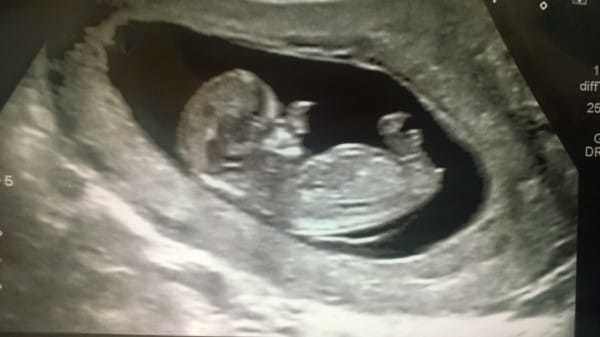

Amy poole, ikinci bebeğine hamileydi. ancak bu sıradan bir hamilelik değildi. doktora gidip ultrasona girdiğinde, hayatının şokunu yaşadı. doktor, 20 haftalık bebeğim yüzünde hiçte normal olmayan bir şeyler görmüştü.